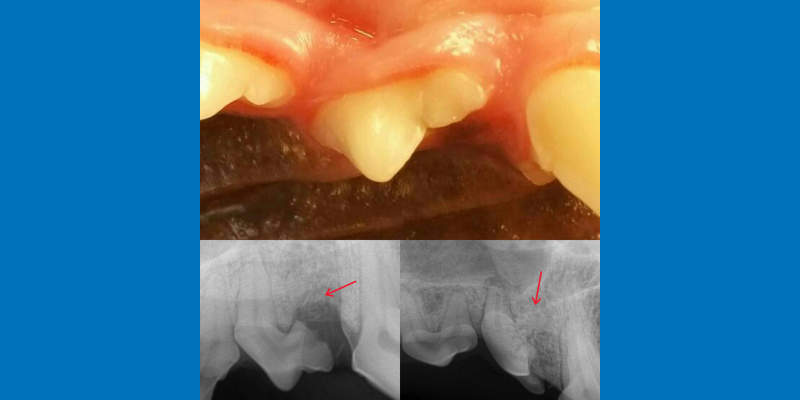

The first premolar appears to be missing on visual exam (left photo, white arrow), but on dental x-ray (right photo) is under the gumline and forming a cyst (red arrow).

In addition, in the next photo, this dog had a missing tooth root. On visual examination, there was no indication at all an underlying problem was lurking. X-rays revealed that one of the tooth roots was completely non-existent. The missing root would have been missed completely if full mouth x-rays hadn’t been taken.